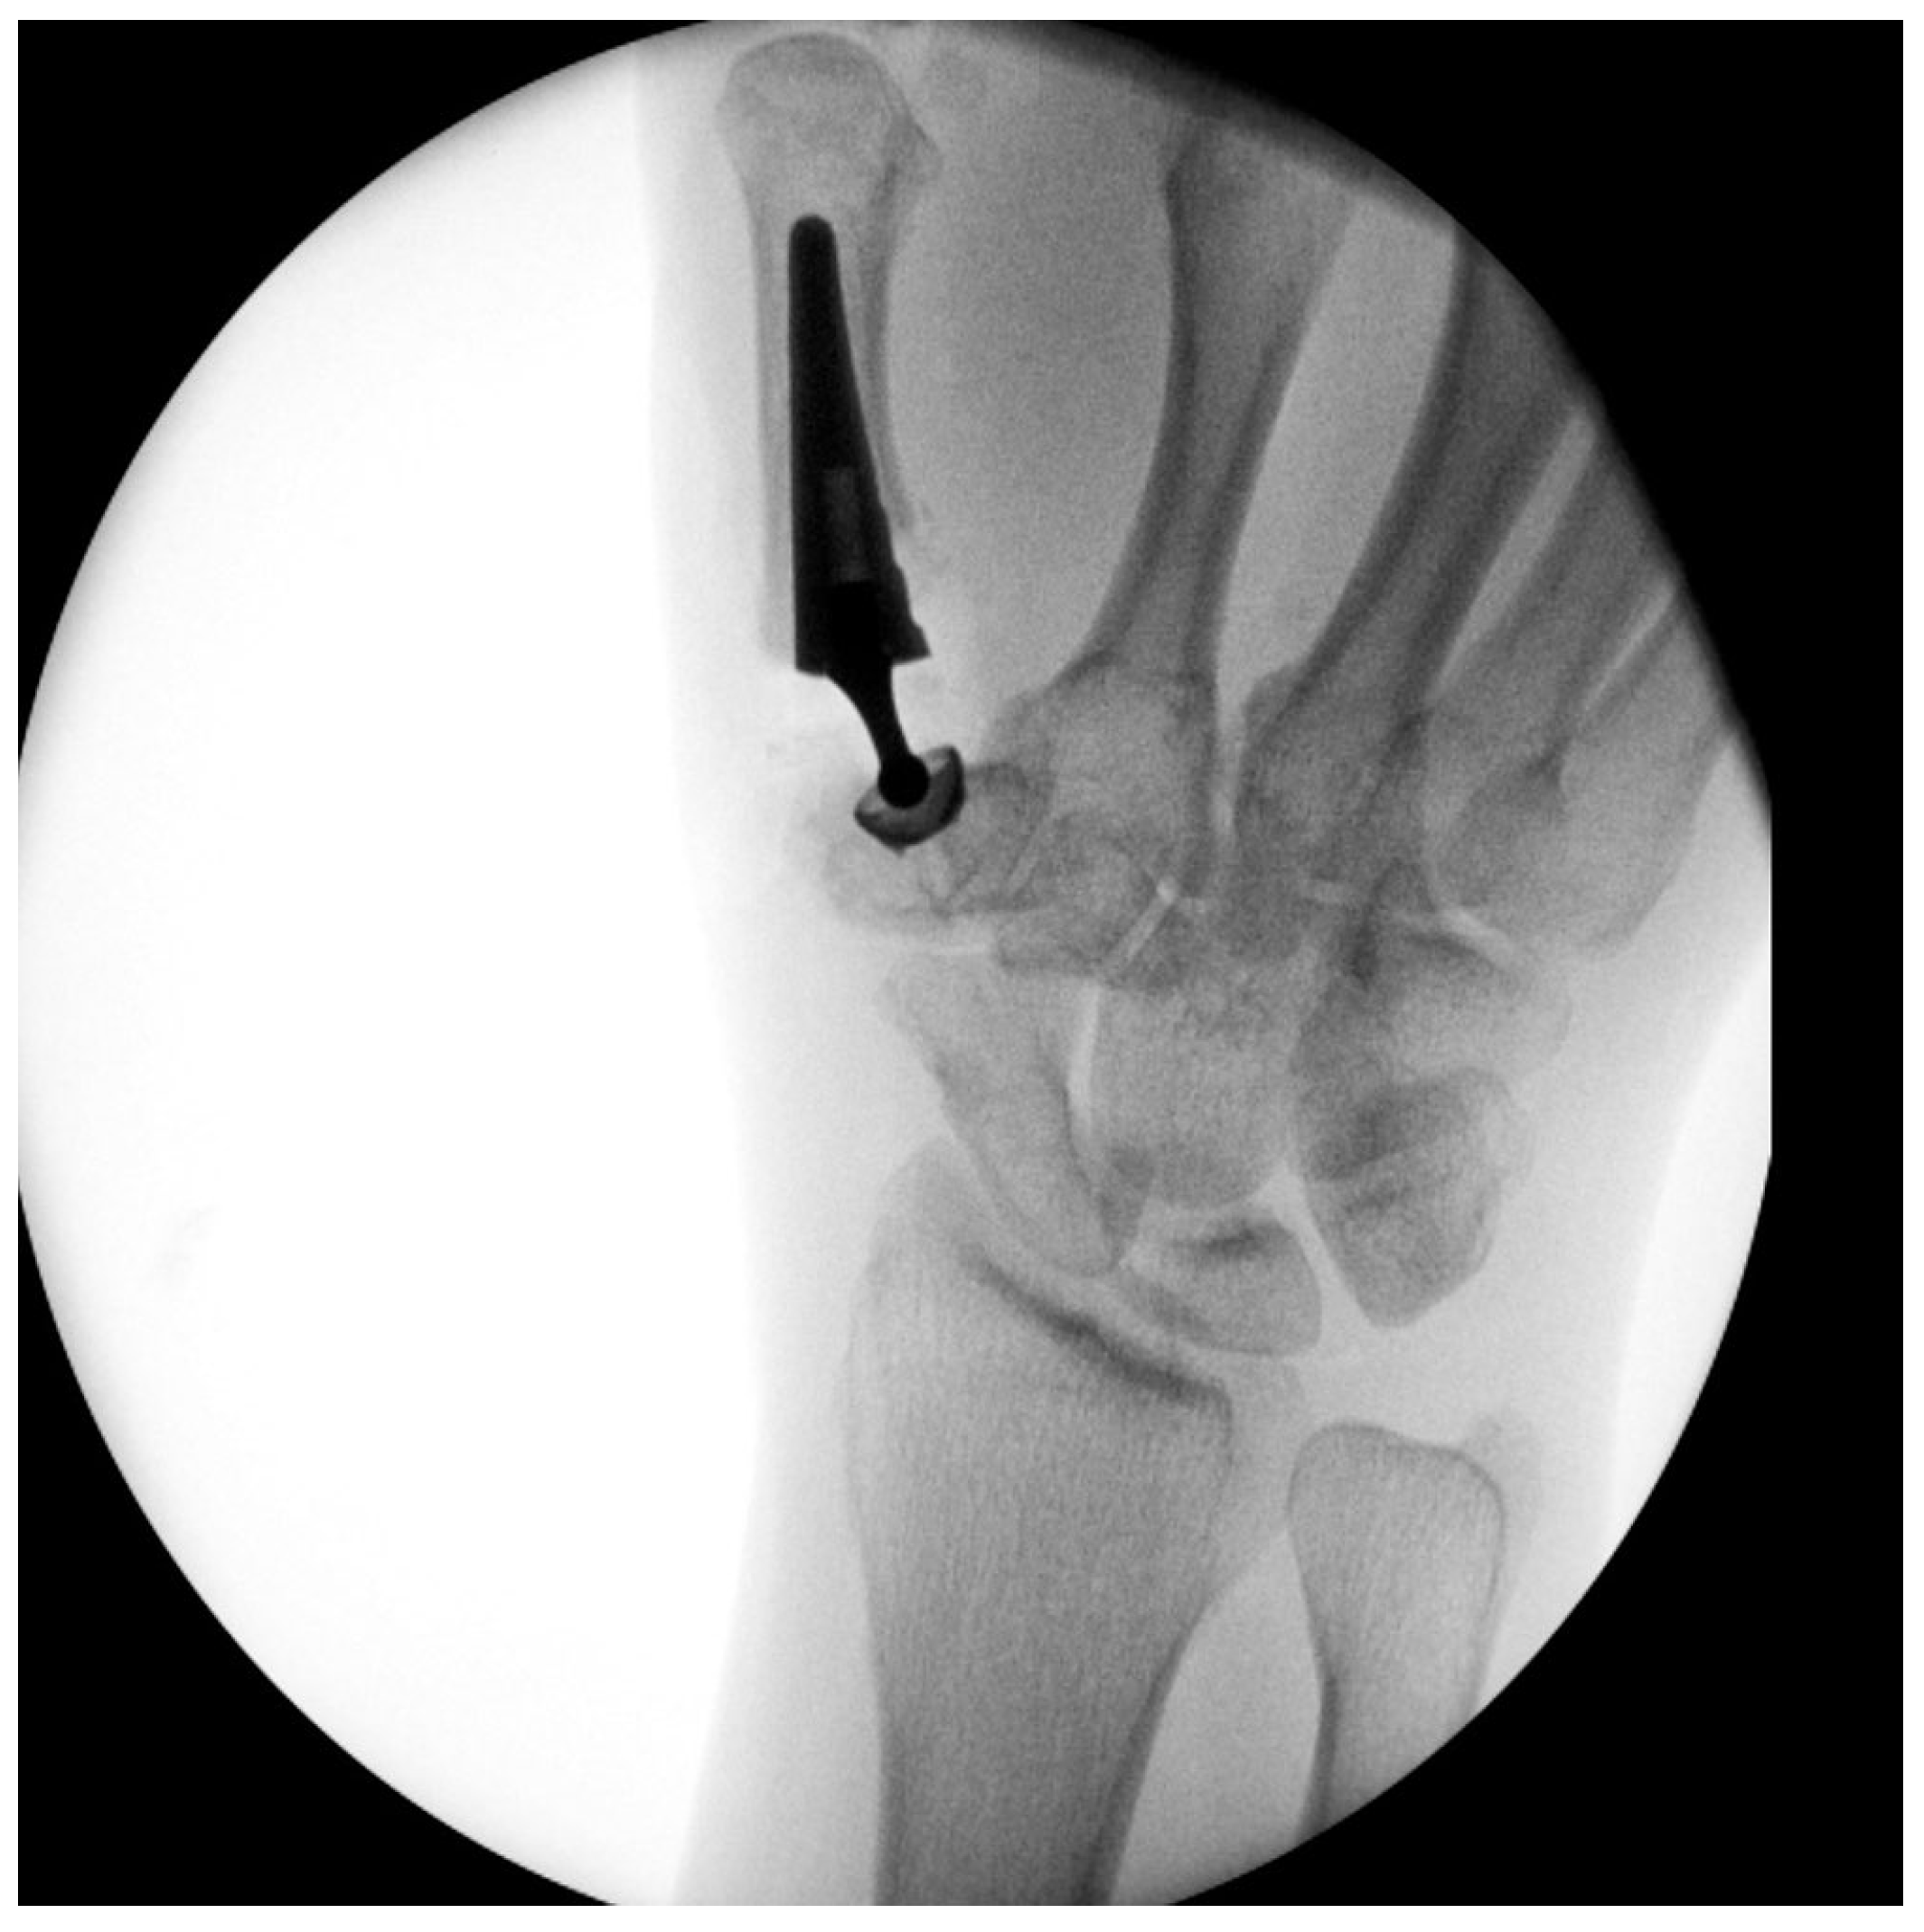

Primary Trapeziometacarpal (TMC) Arthroplasty for Bennett Fracture in Setting of Severe Thumb Osteoarthritis: A Case Report

2. Case Report